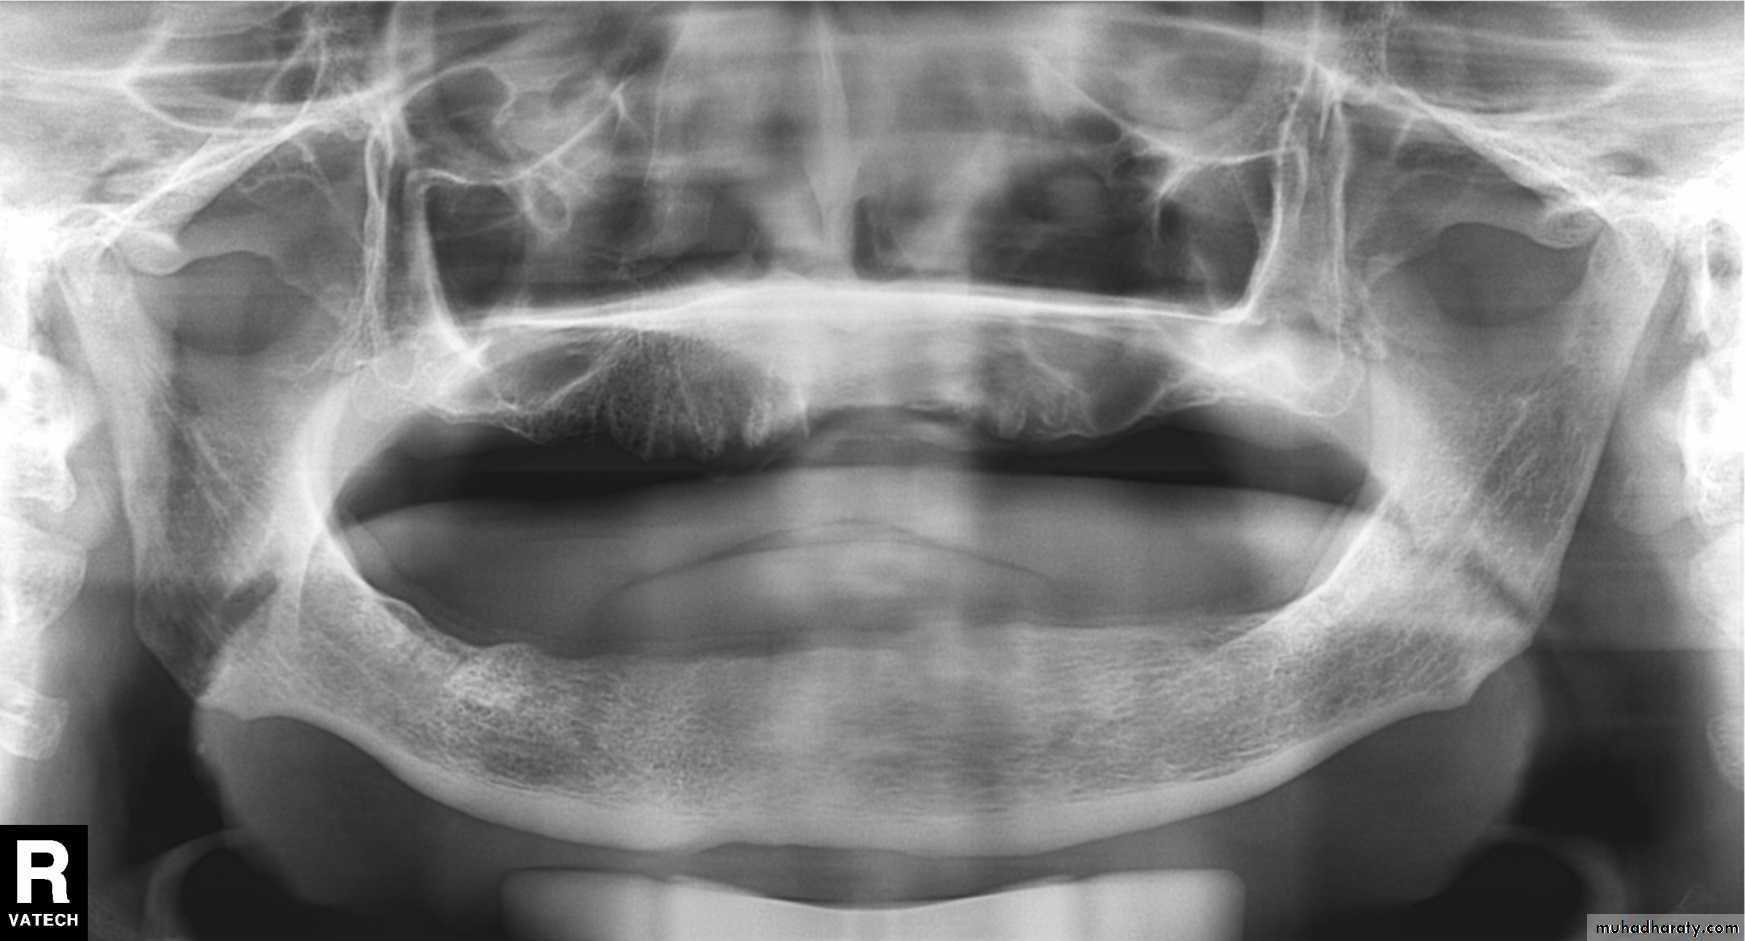

Chin up too high; note flattened occlusal plane, palate superimposed on maxillary tooth roots, and broad flat mandible